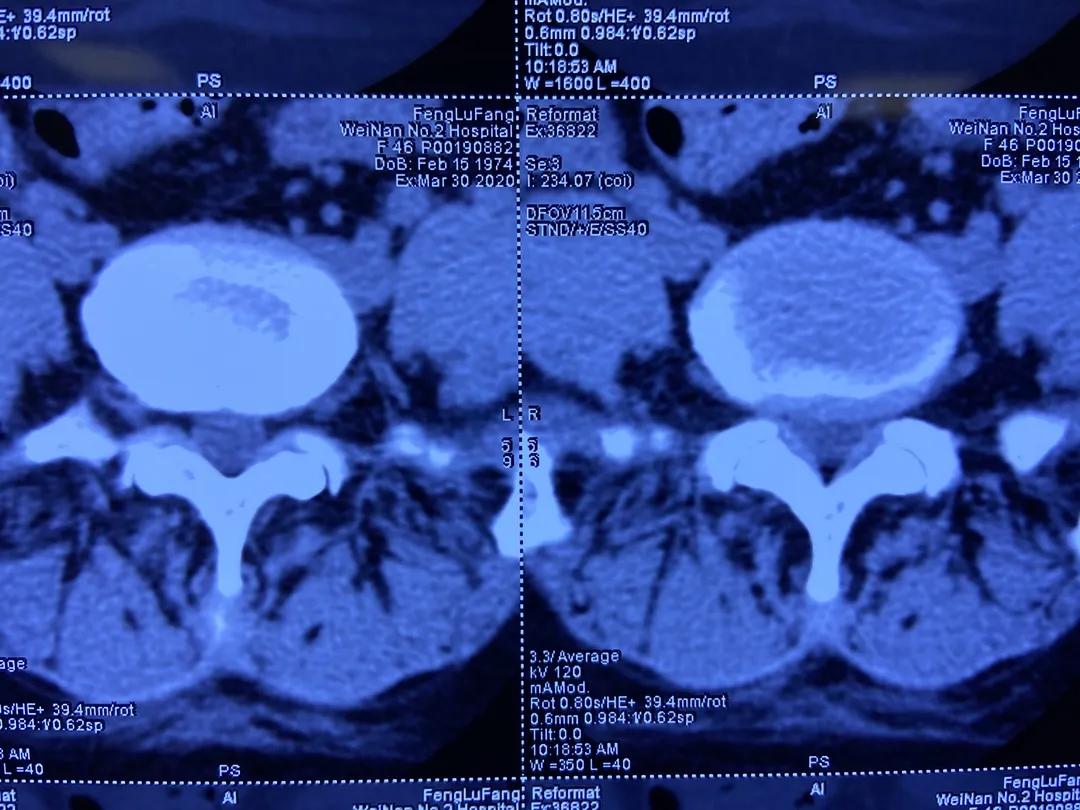

术前CT检查:L5/S1椎间盘突出,黄韧带肥厚。